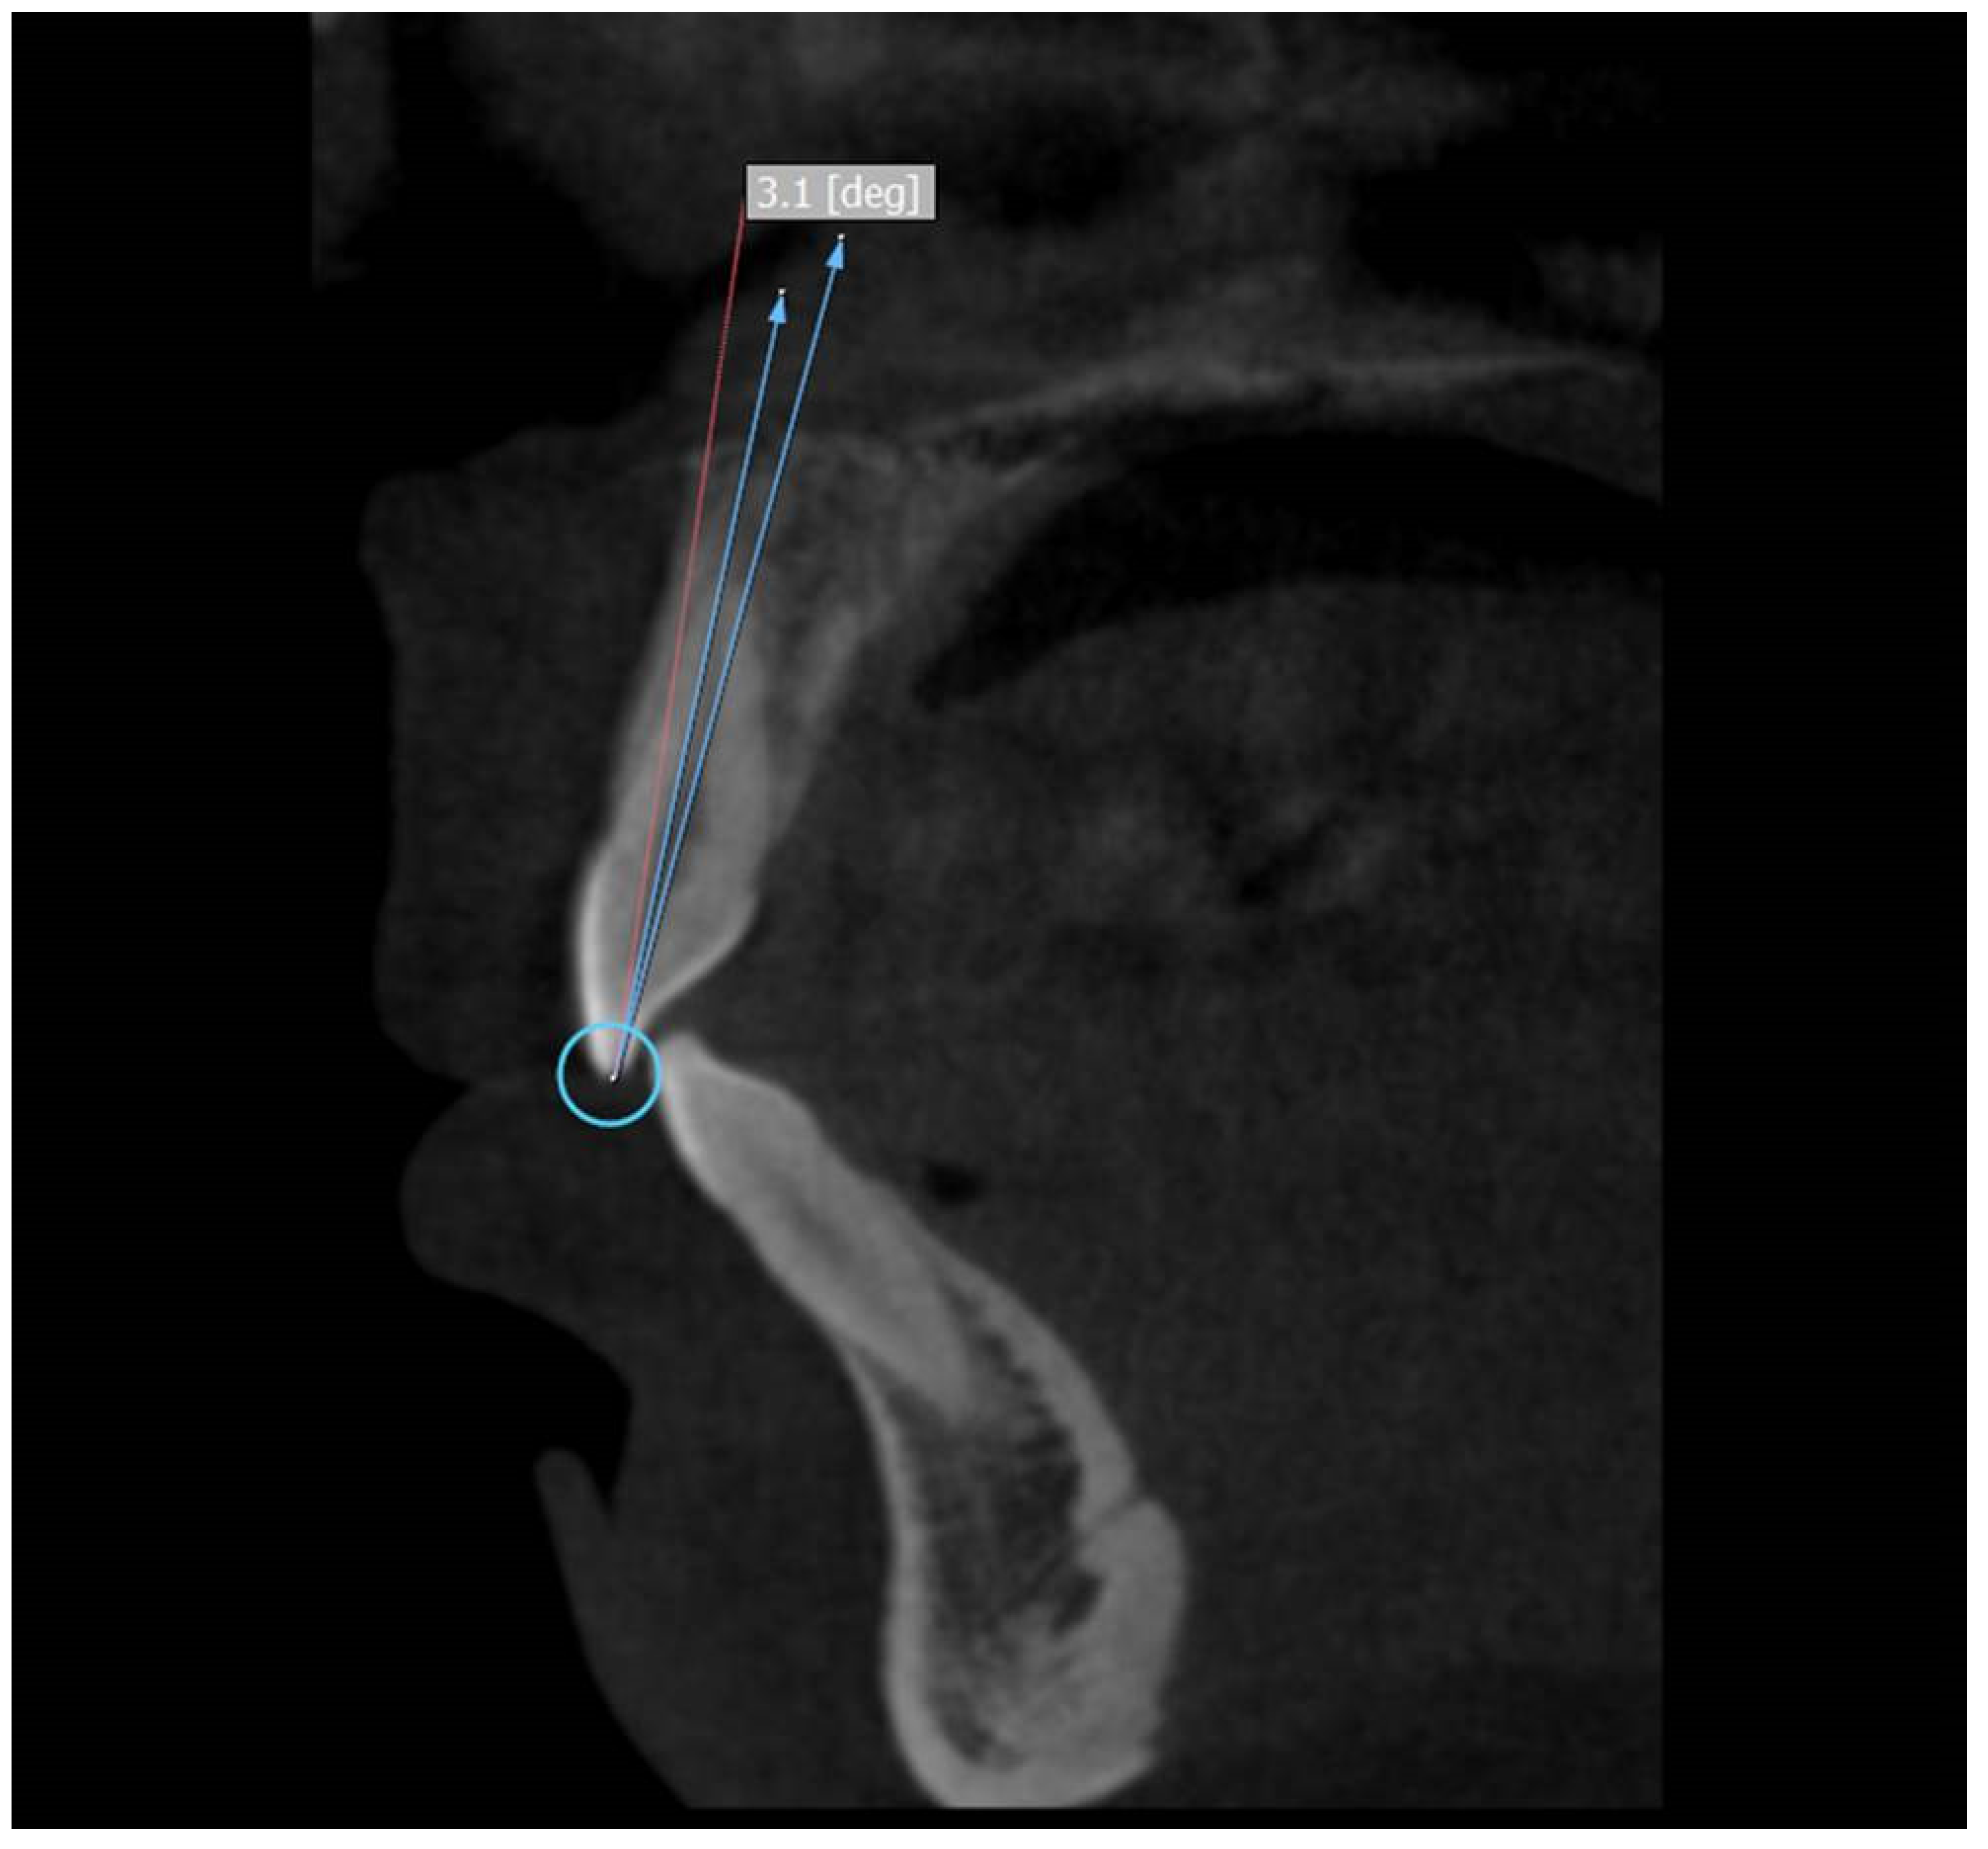

The selected scans were visualized using 3D:OnDemand software. For the axial section of maxilla/mandible, the slices were set to have a thickness of 2.0 mm with slice increments set at 0.1 mm. The axial slice with the best view of the anterior teeth of maxilla/mandible was then chosen. The sagittal slice was created by moving the cursor to the distal and mesial side of the tooth so that the slice is centered on the midline of the tooth. Once the sagittal slice was directly centered on the longitudinal axis, the tooth can then be measured.

Three points were used to measure the crown to root angle (x). Incisor superioris that is an undamaged incisal edge was taken as the first point. A line connecting the facial and the lingual cementoenamel junction was considered as the second point and the third point was the apex of the root [3].

The CA was calculated by subtracting the crown to root angle from 180°. Therefore, the formula for the CA is 180-x. (Figure 1)

Figure 1.

Use of the 3D:OnDemand software to locate the specific points of median sagittal sections for maxillary anterior teeth and to measure crown to root angle.